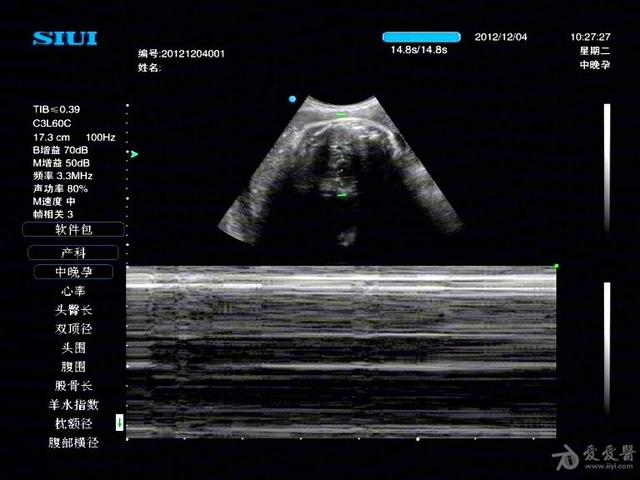

需用高分辨力实时超声诊断仪。常用线阵或凸阵式探头,频率为3~5MHz。仪器如果备有扇扫式探头(3.5MHz)和阴道探头(5~7.5MHz),则更为理想。经腹壁观察位于宫颈或阴道部位病变或当膀胱充盈欠佳时,采用凸阵式或扇扫式探头(配合腹腔壁适当加压扫查)比较有利。改用阴道超声效果更好。增益调节以正常子宫壁呈低水平回声,膀胱内尿液基本上无回声为准。为观察早孕孕囊内胎心、卵黄囊等细微结构时,宜充分放大图像并调节灵敏度。现代彩色超声诊断仪具有B型超声、M型超声、彩色和频谱多普勒超声等多种功能,配有多种探头,是更为理想的仪器。一方面可做常规产科超声检查,另一方面还可高度灵敏地检测血流变化。后者常用于异常妊娠、异位妊娠和滋养体疾病,胎儿各种心血管疾病,脐带异常,胎盘病变等检查。

(二)中晚期妊娠(孕12周以后至分娩前)胎儿检查则无需充盈膀胱。